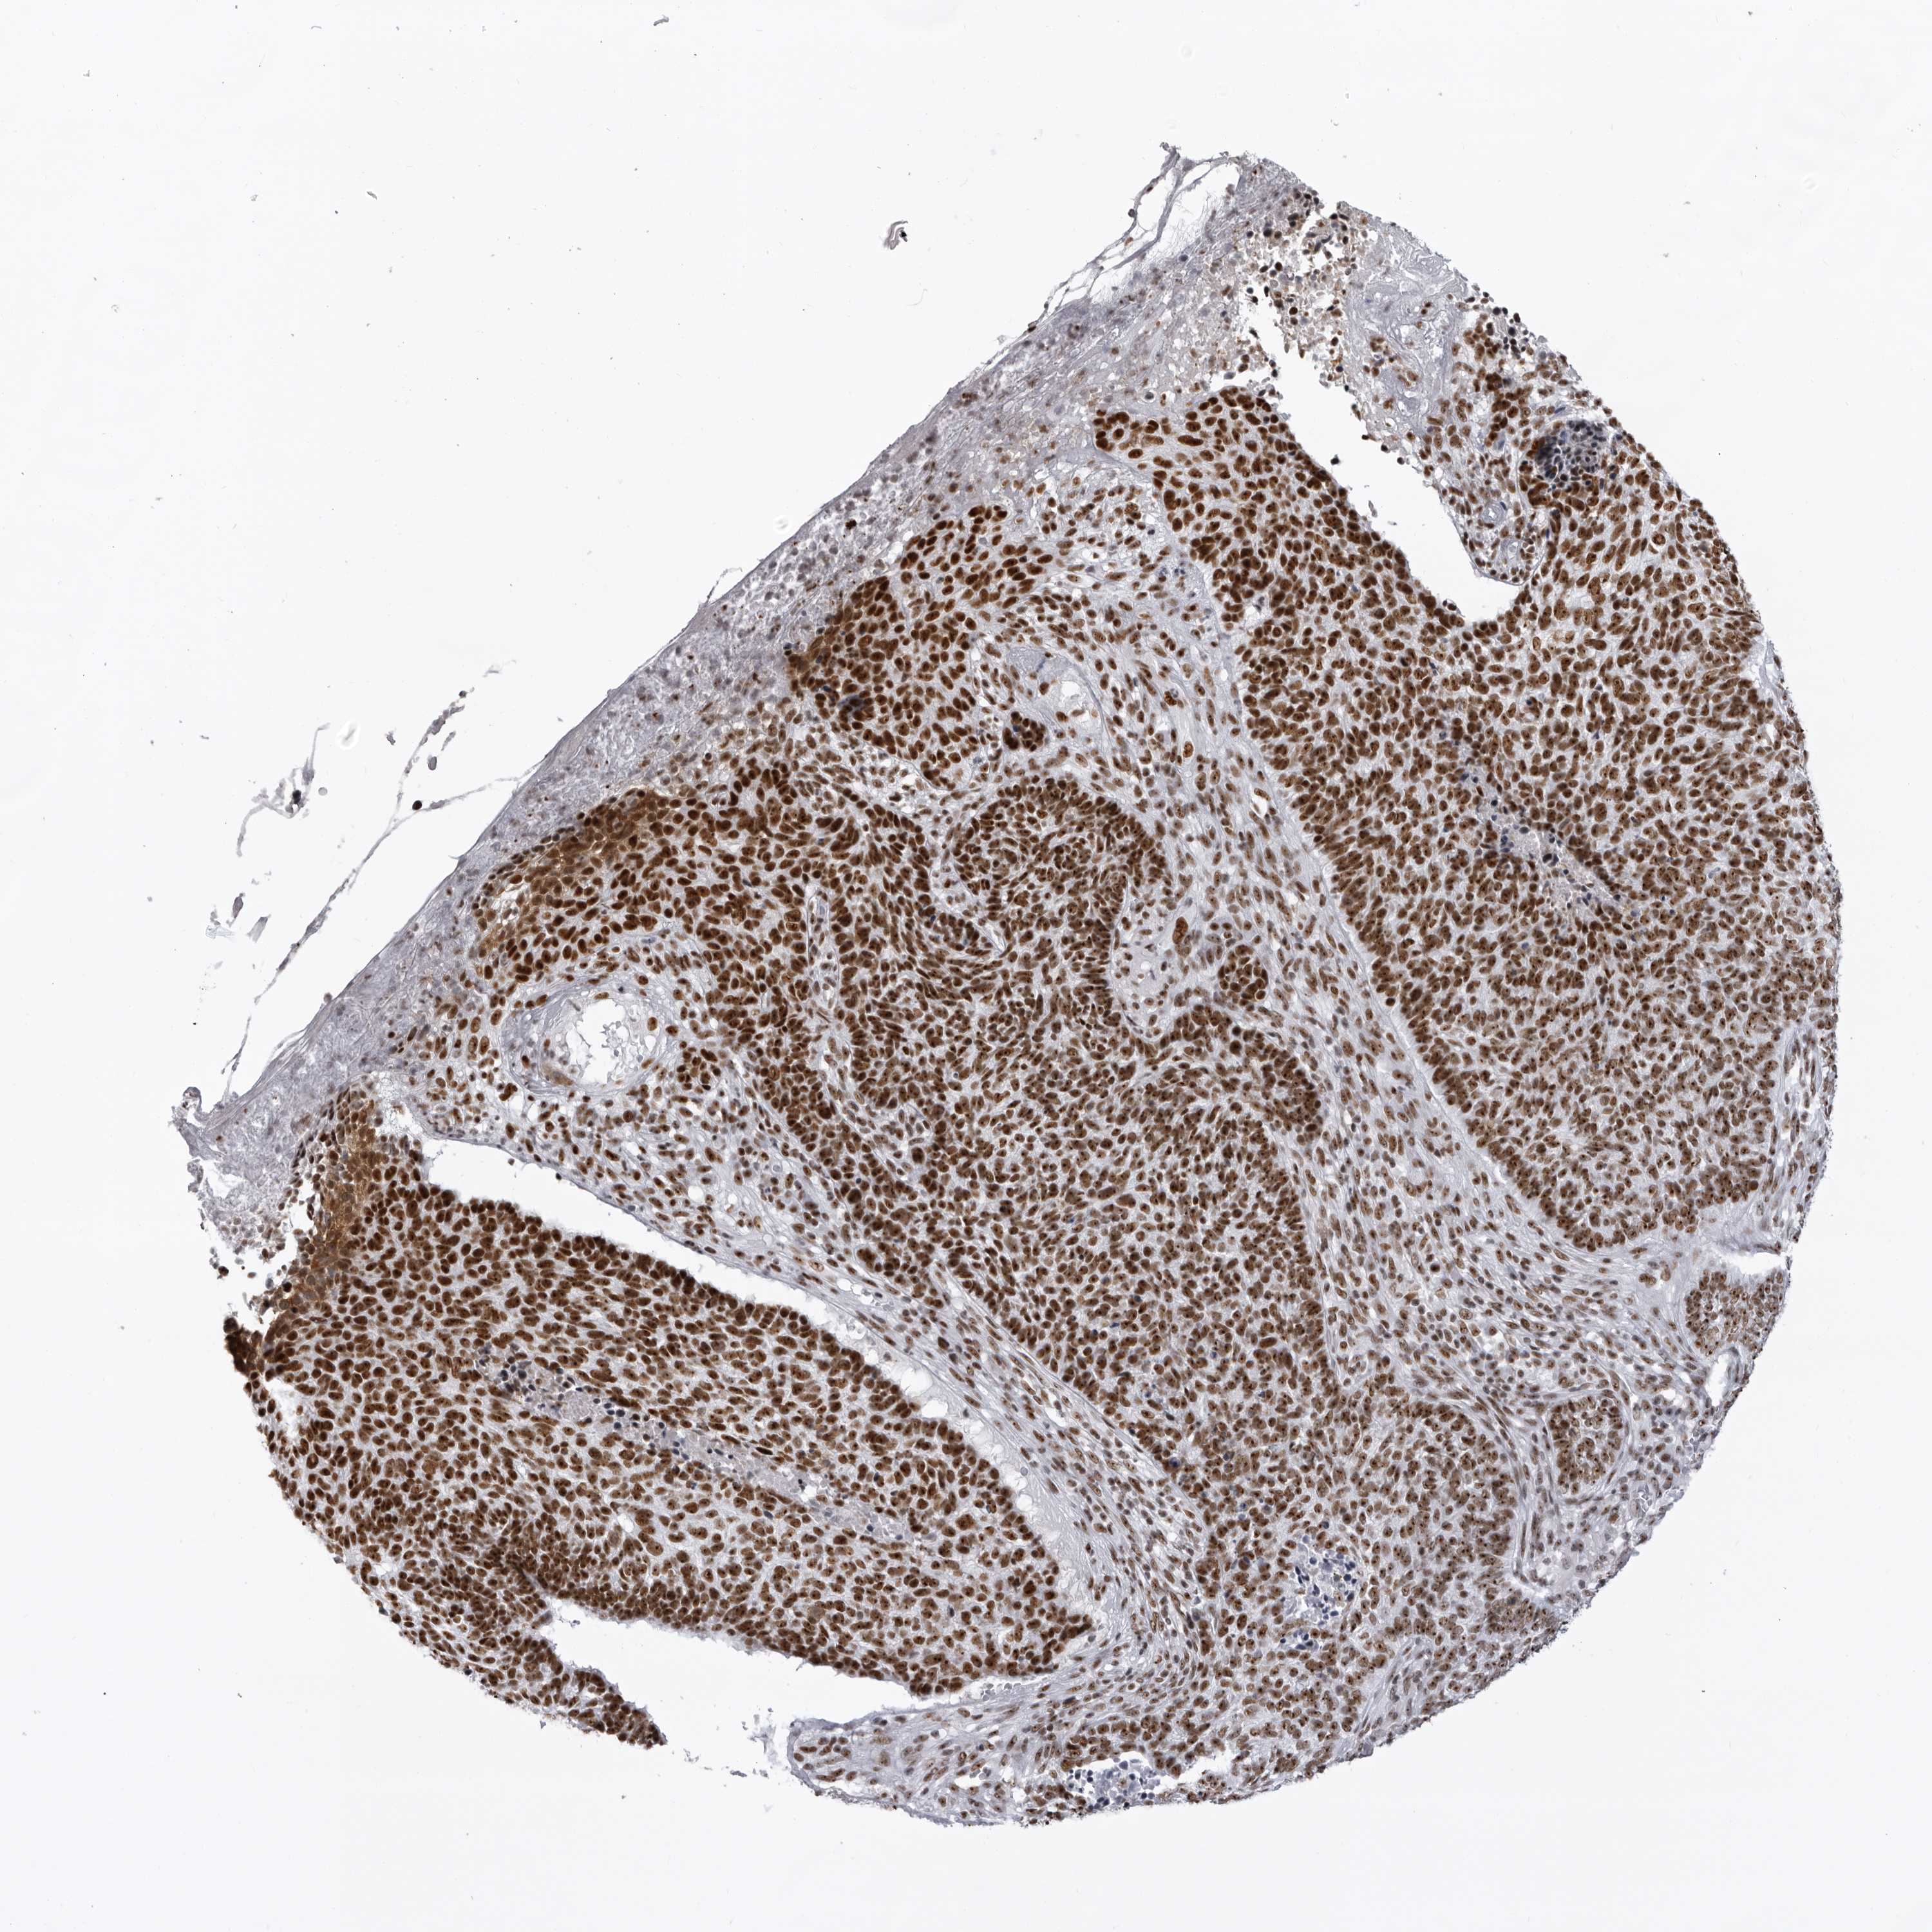

SKIN CANCER - Protein expressioni

A mouse-over function shows sample information and annotation data. Click on an image to view it in a full screen mode. Samples can be filtered based on level of antibody staining by selecting one or several of the following categories: high, medium, low and not detected. The assay and annotation is described here.

Each image is clickable and will lead to virtual microscopy that enables deeper exploration of all samples and also displays staining intensity scores, fraction scores and subcellular localization as well as patient and tissue information for each sample.

Antibody CAB011819

High

Intensity

Strong

Quantity

>75%

Location

Nuclear

Squamous cell carcinoma, NOS